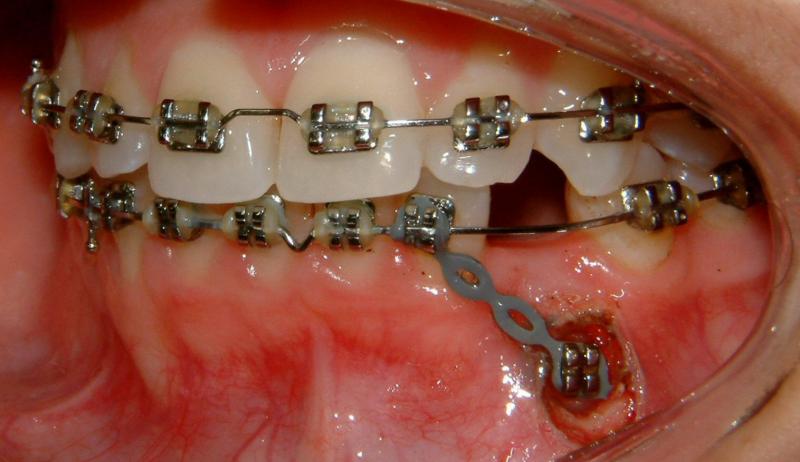

With the surgical exposure (a diode laser for soft tissue, a round bur for bone; practically no bleeding, same day) and forced eruption - immediate pulling (gently), the progress is expected to be seen rapidly (Fig. 19).

Fig. 19 Right after surgery (same day), no bleeding - immediate pulling (gently)

© Copyright 2007-2014, Vu Orthodontics. All rights reserved.

In the 1st post-op visit (2 days after the surgery), healing is seen in progress (Fig. 20).

Fig. 20 First post-op visit, 2 days after surgical exposure (progress, good healing)